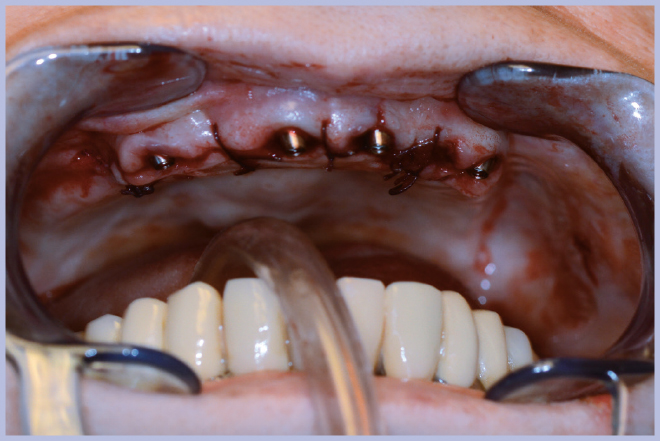

Dopo l’estrazione dei 3 elementi residui (Fig. 2), sono stati posizionati 4 impianti Max Stability Ø3,75 mm (2 di lunghezza 10 mm e 2 di lunghezza 12 mm).

- Fig. 2 – Elementi residui prima dell’estrazione